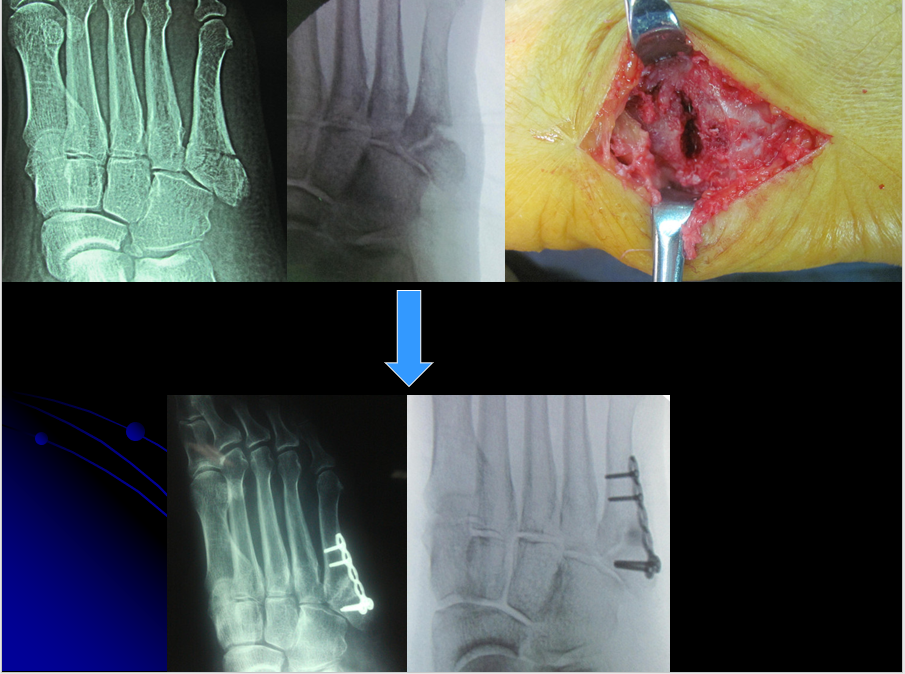

第二种手术治疗方法有:内固定伴植骨,空心钉、张力带、钩钢板等。

1)传统内固定方式:

• 克氏针及张力带固定

• 空心螺钉固定

• 空心螺钉髓内固定

• 微型锁定接骨板固定

• 骑缝钉固定

• 微型钩钢板固定

微型锁定钢板螺钉固定固定坚强,术后可以佩戴前足减压支具早期活动 ,适用于骨块较大,要求较高的患者。弊端是费用较高,需二次取出。

操作要点:板钉直径以2.0 mm为宜,远近端至少保证2枚螺钉。

微型钩钢板固定——一种新的有效手术方法适用于第五跖骨基底部I区和II区骨折(移位﹥2毫米)或者伴有小的粉碎型撕脱骨折块。

第五跖骨基底骨折应用钩钢板固定法治疗更为牢固可靠,且应力性能好;对于粉碎骨折、移位较明显的骨折,钩钢板法尤其具有明显优势,钩钢板的尖头钩可牢固抓持粉碎骨块,实现可靠复位,能更有效缩短患者住院时间、促进骨折愈合、恢复患足功能、促进早期功能锻炼,疗效显著且安全性高,是治疗第五跖骨基底骨折的一种安全有效的方案。

设计:微型管状的钩板的最后一个孔被设计成可充当用于压缩作用的钩,抓粉碎骨折块,防止移位,并且在基底部可以控制旋转稳定。